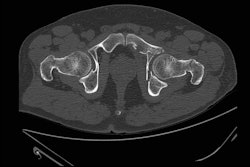

"This was torture," Bryan explained. Adoption of CT came pretty rapidly thereafter; however, it took at least five years before industry could provide enough instruments to meet clinical demand. Bryan and Jha discuss the significance of CT at the time.

A noncontrast EMI-CT scan took about 48 minutes for 16 slices, and 3 minutes to read. "Now you have the opposite problem," Bryan said, noting that a typical brain neuro noncontrast head CT presents no less than 60 to 100 images. A CT scan now takes around 30 seconds, and scans are scheduled for about every 15 minutes at the slowest, he explained.